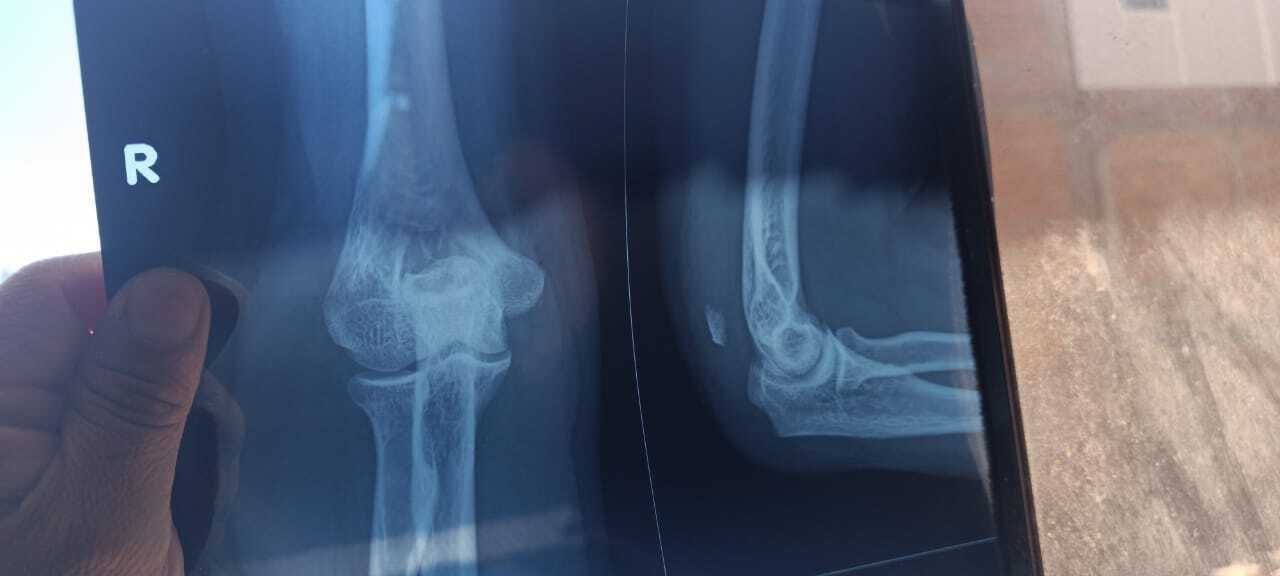

A Bible College student, Johnatan Roca, just severely broke his arm and tore the tendons. He has to have immediate surgery. The cost is 8,000 Peruvian soles. That is $2,151 US$. He does not have insurance. His dad, Richard Roca, is a very faithful pastor.